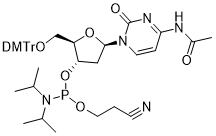

馬鞍山致研生物醫(yī)藥科技有限公司成立于馬鞍山市鄭浦港新區(qū)現(xiàn)代產(chǎn)業(yè)園。公司專(zhuān)注于生物小分子、醫(yī)藥中間體相關(guān)產(chǎn)品的研發(fā)和生產(chǎn),產(chǎn)品主要包括DNA亞磷酰胺單體、RNA亞磷酰胺單體、特殊單體以及按照客戶(hù)要求定制的RNA和DNA,并且公司提供定制合成等方面的研究服...

馬鞍山致研生物醫(yī)藥科技有限公司成立于馬鞍山市鄭浦港新區(qū)現(xiàn)代產(chǎn)業(yè)園。公司專(zhuān)注于生物小分子、醫(yī)藥中間體相關(guān)產(chǎn)品的研發(fā)和生產(chǎn),產(chǎn)品主要包括DNA亞磷酰胺單體、RNA亞磷酰胺單體、特殊單體以及按照客戶(hù)要求定制的RNA和DNA,并且公司提供定制合成等方面的研究服...